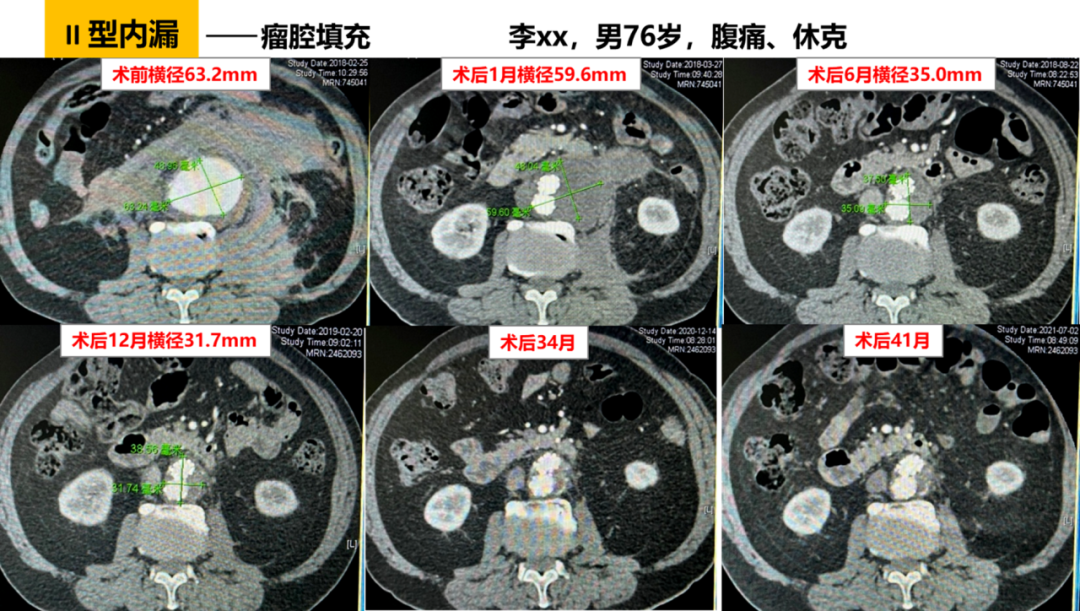

自 2018 年起,我院在 EVAR 术中常规 预置导管至瘤腔,释放支架后立即 注入凝血酶,诱导瘤腔内生理性血栓形成。

初步成果(70 余例随访):

II 型内漏发生率显著降低;

动脉瘤囊回缩速度明显快于传统组(1 个月即可见显著缩小,6 个月更明显);

无过敏、异位栓塞或感染等并发症(得益于严格操作质控)。